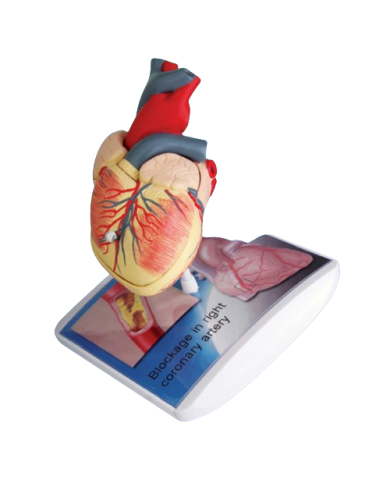

Modello anatomico PER FORNITURE CASE FARMACEUTICHE

Modello anatomico PER FORNITURE CASE FARMACEUTICHE

Modello anatomico PER FORNITURE CASE FARMACEUTICHE

Modello anatomico PER FORNITURE CASE FARMACEUTICHE

Modello anatomico PER FORNITURE CASE FARMACEUTICHE

Modello anatomico PER FORNITURE CASE FARMACEUTICHE

Modello anatomico PER FORNITURE CASE FARMACEUTICHE

Modello anatomico PER FORNITURE CASE FARMACEUTICHE

Modello anatomico PER FORNITURE CASE FARMACEUTICHE

Modello anatomico PER FORNITURE CASE FARMACEUTICHE

Modello anatomico PER FORNITURE CASE FARMACEUTICHE

Modello anatomico PER FORNITURE CASE FARMACEUTICHE

Modello anatomico PER FORNITURE CASE FARMACEUTICHE

Modello anatomico PER FORNITURE CASE FARMACEUTICHE

Modello anatomico PER FORNITURE CASE FARMACEUTICHE

Modello anatomico PER FORNITURE CASE FARMACEUTICHE

Modello anatomico PER FORNITURE CASE FARMACEUTICHE

Modello anatomico PER FORNITURE CASE FARMACEUTICHE

Modello anatomico PER FORNITURE CASE FARMACEUTICHE

Modello anatomico PER FORNITURE CASE FARMACEUTICHE

Modello anatomico PER FORNITURE CASE FARMACEUTICHE

Modello anatomico PER FORNITURE CASE FARMACEUTICHE